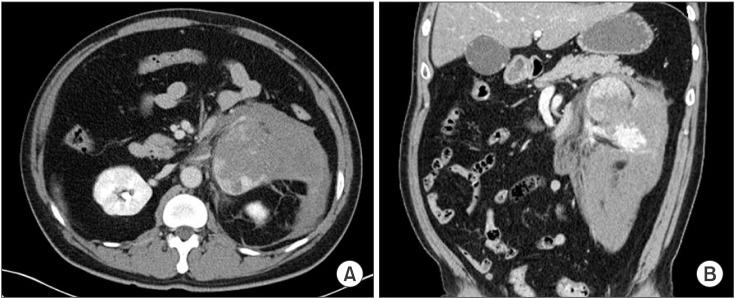

Ruptured pheochromocytoma is a rare disease. Its mortality rate is up to 31%-50%. Proper management of ruptured pheochromocytoma remains unclear. A 44-year-old male patient visited our Emergency Department and presented with abrupt onset of left flank pain. His blood pressure was 190/140 mmHg with purse rate of 130 beats/min. CT scan showed 8.1 × 5.6-cm-sized heterogeneously mass with rupture on the left retroperitoneal space and active bleeding. His symptom of abdominal pain was aggravated. Follow-up laboratory analysis revealed elevated WBC count and decreased hemoglobin 2 hours after admission. Emergency laparotomy was performed. We resected the ruptured left retroperitoneal mass and hemostasis. Pathologic exams revealed adrenal pheochromocytoma with rupture. Although our patient was alive, according to literature review, mortality rate of emergency operation without medical management is higher than elective operation after blood pressure control with either medical or interventional methods such as transcatheter arterial embolization.

嗜铬细胞瘤破裂是一种罕见疾病。其死亡率高达31% - 50%。嗜铬细胞瘤破裂的恰当处理方法仍不明确。一名44岁男性患者就诊于我院急诊科,表现为突发左侧腰痛。其血压为190/140 mmHg,心率为130次/分钟。CT扫描显示左腹膜后间隙有一个大小为8.1×5.6 cm的不均匀肿块,伴有破裂及活动性出血。他的腹痛症状加重。入院2小时后的后续实验室分析显示白细胞计数升高,血红蛋白降低。遂进行了急诊剖腹手术。我们切除了破裂的左腹膜后肿块并进行了止血。病理检查显示为肾上腺嗜铬细胞瘤伴破裂。尽管我们的患者存活了下来,但根据文献综述,未进行药物治疗的急诊手术死亡率高于在通过药物或诸如经导管动脉栓塞等介入方法控制血压后进行的择期手术。